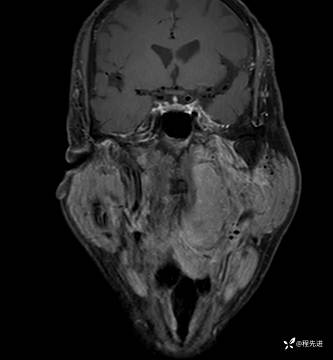

MRI平扫+增强:

T1增强: